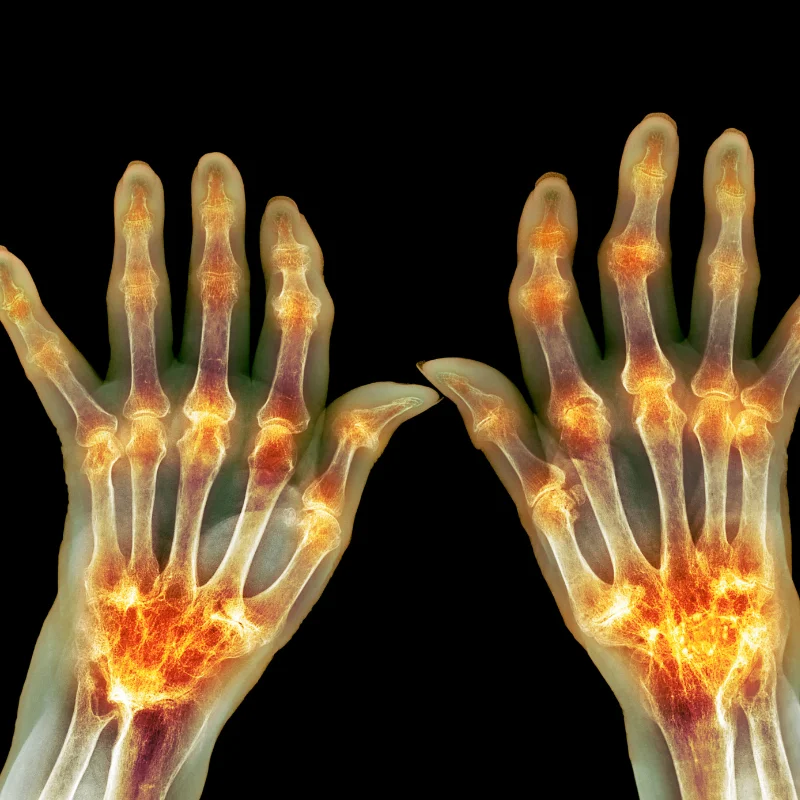

Rheumatoid arthritis is an autoimmune inflammatory disease in which synovial inflammation can drive pain, swelling, stiffness, structural damage, and systemic complications. Earlier researchers focused on the role of immune complexes, autoantibodies, and other circulating inflammatory mediators. That made plasmapheresis appealing in theory because the procedure can physically remove a portion of plasma and the substances carried in it (Seror et al., Transfusion and Apheresis Science, 2007).